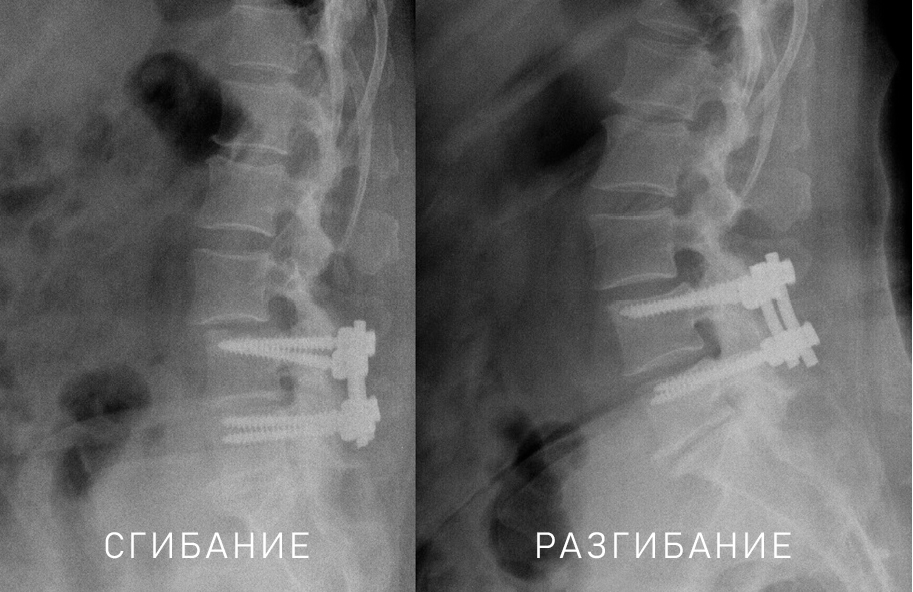

Вторым критерием, который оценивают при проведении функциональных спондилограмм ПОП, представляется угол между замыкательными пластинками позвонков заинтересованного ПДС. Угол, превышающий 10°, считают признаком нестабильности ПДС. В научной литературе распространенным термином, обозначающим данный угол, является термин «ангуляция» [23]. Ochia R.S. et al. предлагают критериями нестабильности считать ангуляцию более 4°, трансляцию более 6 мм [24]. В настоящее время сегментарная нестабильность, выявляемая при функциональной спондилографии, определяется критериями White А.А. и Panjabi М.М.: сагиттальная трансляционная более 4 мм или 15% и/или боковая ангуляция более 10° (рисунки 1 и 2) [2, 25].

Рисунок 1. Функциональная спондилография ПОП. В ПДС L4-5 визуализируется сагиттальная трансляция более 4 мм.

Рисунок 2. Функциональная спондилография ПОП. Больной ранее перенес спондилодез ПДС L4-5. В отдаленном послеоперационном периоде развился синдром смежного уровня в виде нестабильности в ПДС L3-4. В ПДС отмечается сагиттальная трансляция более 4 мм и боковая ангуляция.

Проблемой оценки нестабильности при функциональной спондилографии может явиться болевой синдром и/или мышечно-тонический синдром, которые могут не позволить пациенту полностью выполнить сгибание и разгибание ПОП [1, 7].